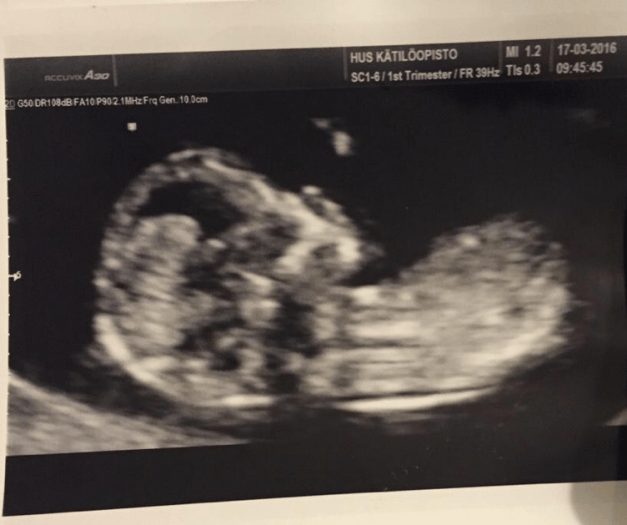

很快就到了孕中期,5個月的時候B超可以看性別了,我們倆都特別期待,在照B超的時候醫生跟我們説,大概率是女孩。於是我們就想着給寶寶起名字啦。某一天我一拍腦袋,小名就叫miumiu吧,聽起來是個挺可愛的女孩兒名。

圖:miumiu的B超照片